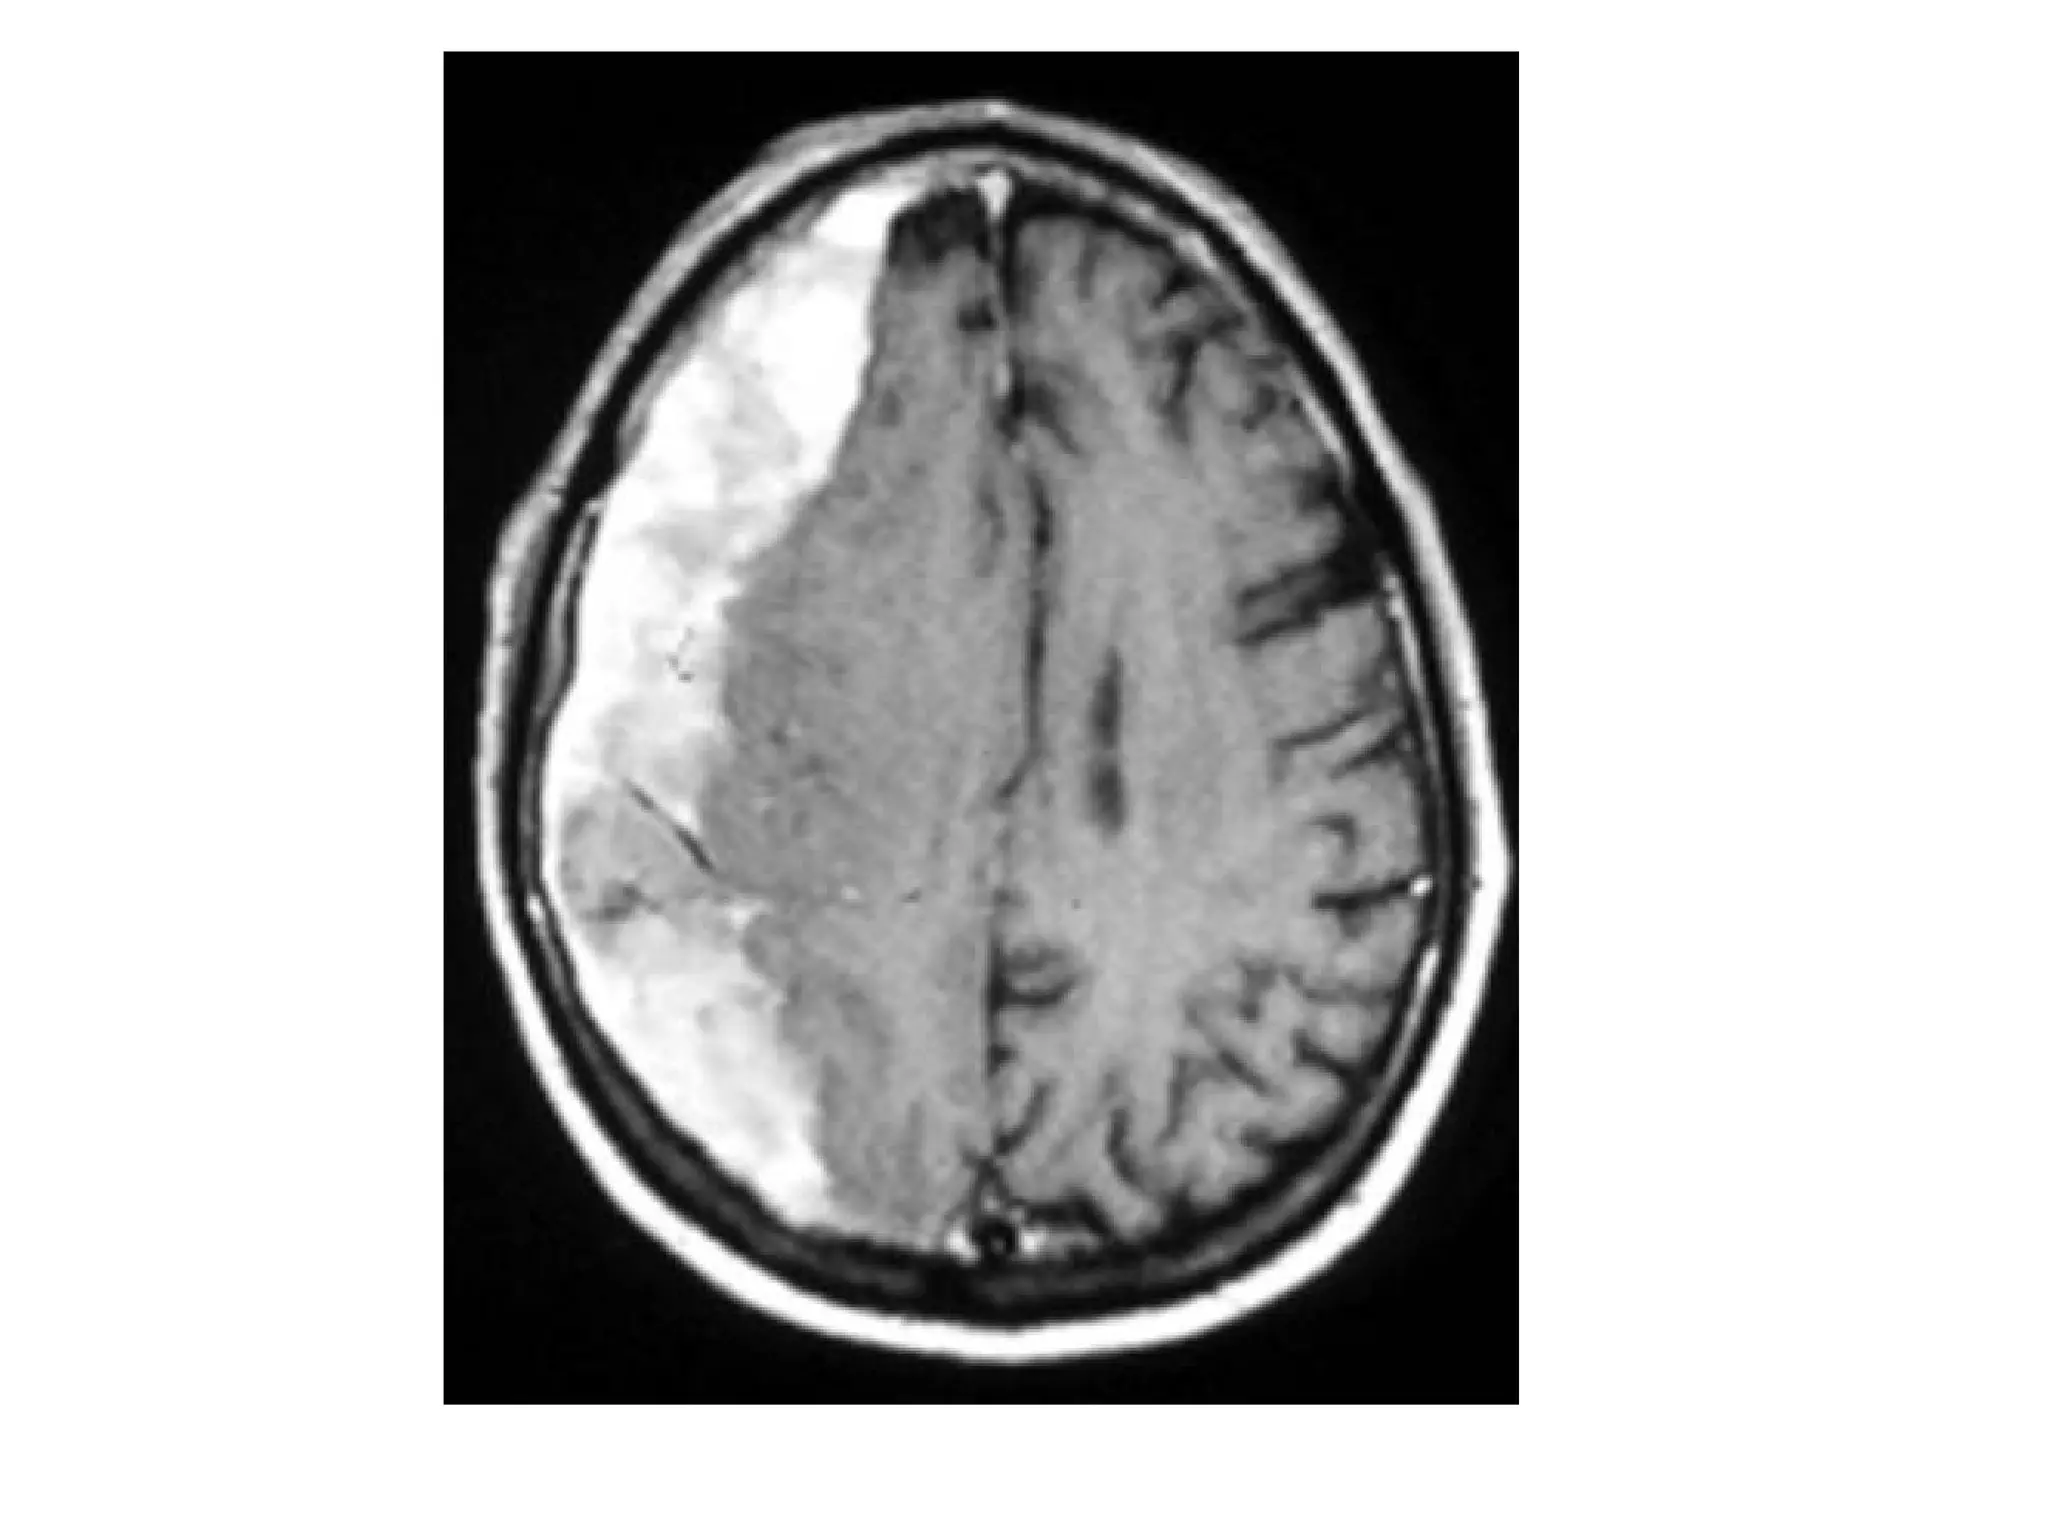

2-Bilateral Infarcts :

-Venous infarcts are often bilateral in the midline and

hemorrhagic

-Occlusion of the midline veins (deep cerebral veins “

Internal cerebral veins and basal veins of Rosenthal

“ , straight sinus & SSS) may result in bilateral areas of

low attenuation on CT and increased T2

-Thrombosis of the deep cerebral veins may involve the

basal ganglia , thalami , midbrain and mesial temporal

lobes in a relatively symmetrical fashion

-The most frequently thrombosed venous

structure is the SSS , infarction is seen in 75%

of cases , the abnormalities are parasagittal

and frequently bilateral , hemorrhage is seen

in 60% of the cases

Bilateral infarction in superior sagittal sinus thrombosis